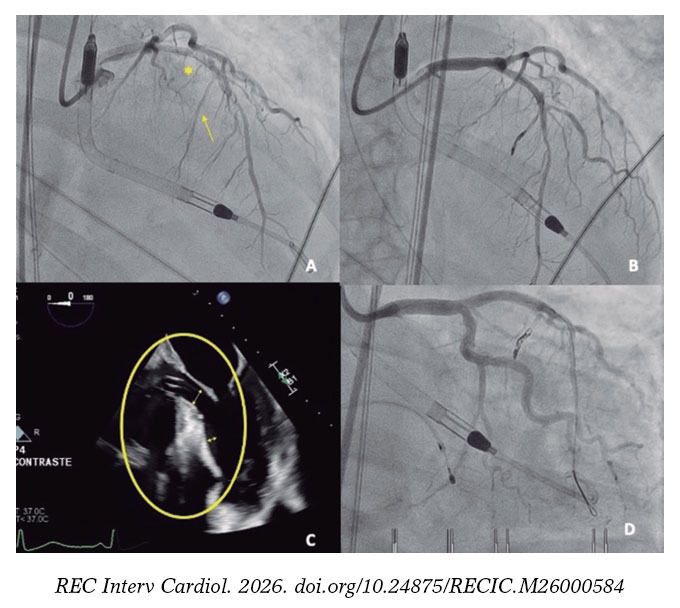

Una mujer de 77 años ingresó por síndrome coronario agudo sin elevación del segmento ST de clase Killip-III. El cateterismo emergente mostró una lesión crónica no oclusiva en la descendente anterior media, que se trató. La evolución, tras recuperar la fracción de eyección del ventrículo izquierdo, sugería síndrome de tako-tsubo (figura 1A,B).

A pesar de la administración de fluidoterapia y esmolol para disminuir la obstrucción dinámica del tracto de salida del ventrículo izquierdo (ODTSVI), progresó a shock cardiogénico SCAI-D y requirió vasopresores, intubación e implante de balón de contrapulsación aórtico en ratio 1:3 para evitar exacerbar la ODTSVI. Ante el continuo deterioro, se decidió escalar a Impella CP (Abiomed, Inc., EE.UU.) como puente a la recuperación. Se descartó afección mitral orgánica y, considerando la insuficiencia mitral secundaria al movimiento sistólico anterior (figura 1C, vídeo S1), se planificó una ablación septal emergente.

El implante del dispositivo Imp ella-CP (figura 1D, asterisco) ajustando un flujo de 2,4 l/min (P4) para evitar la succión, produjo una mejora hemodinámica y respiratoria inmediata, con disminución de la insuficiencia mitral (figura 1E,F, flechas: onda S sistólica). Una segunda rama septal (RS) mostraba compresión extrínseca, y se seleccionó tras confirmar la irrigación septal (figura 2A, flecha: segunda RS; asterisco: primera RS). Se implantaron 2 coils (figura 2B) por la potencial reversibilidad, con reducción inmediata del flujo y reducción de ODTSVI.